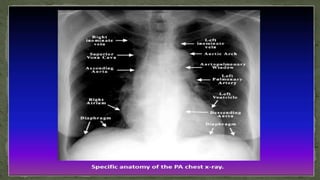

1. TRACHEA

 It should be central or slightly deviated to the right.

- In case of deviation decide if is due to rotation or pathology

 View the carina, angle should be between 60 –100 degrees.

 Because it contains air, it appears darker

(blacker/radiolucent).

 Trachea normally narrows at the vocal cords (T3/T4)

6. HEMIDIAPHRAGM

7. HEART

• The heart lies more to the left of the thoracic cavity.

• The heart is assessed by means of the cardio-thoracic ratio

(CTR).

• CTR = Cardiac width : Thoracic width

• CTR > 50% is abnormal – PA view only

• The left hemidiaphragm should be visible behind the heart.

• The hemidiaphrams do not represent the lowest point of the

lungs.

8. THE MEDIASTINUM

• The mediastinum contains the heart and great vessels (Middle

mediastinum) and potential spaces in front of the heart (anterior

mediastinum), behind the heart (Posterior mediastinum) and above

the heart (superior mediastinum).

• These potential spaces are not defined on a normal CXR, but their

awareness can help in describing location of disease processes.

• There are several structures in the superior mediastinum that should

always be checked. These include aortic knuckle, aorto-pulmonary

window and the right para-tracheal stripe.